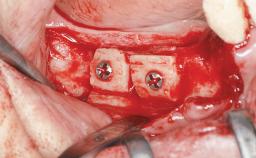

Guided Bone Regeneration (GBR) with a Particulated Autologous Graft and a ePTFE-Reinforced Membrane for Vertical Augmentation of a Single-Tooth Edentulous Space in the Esthetic Zone

Bone Augmentation Staged|Vertical

Augmentation Materials Autogenous chips|Membrane